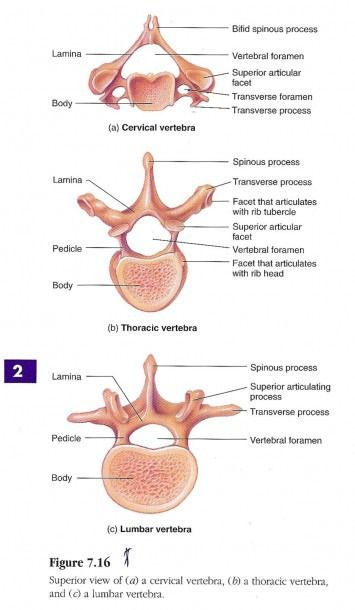

Types of Vertebra

Spiny Process

Pedicles

Lamina

Vertebral Foramen